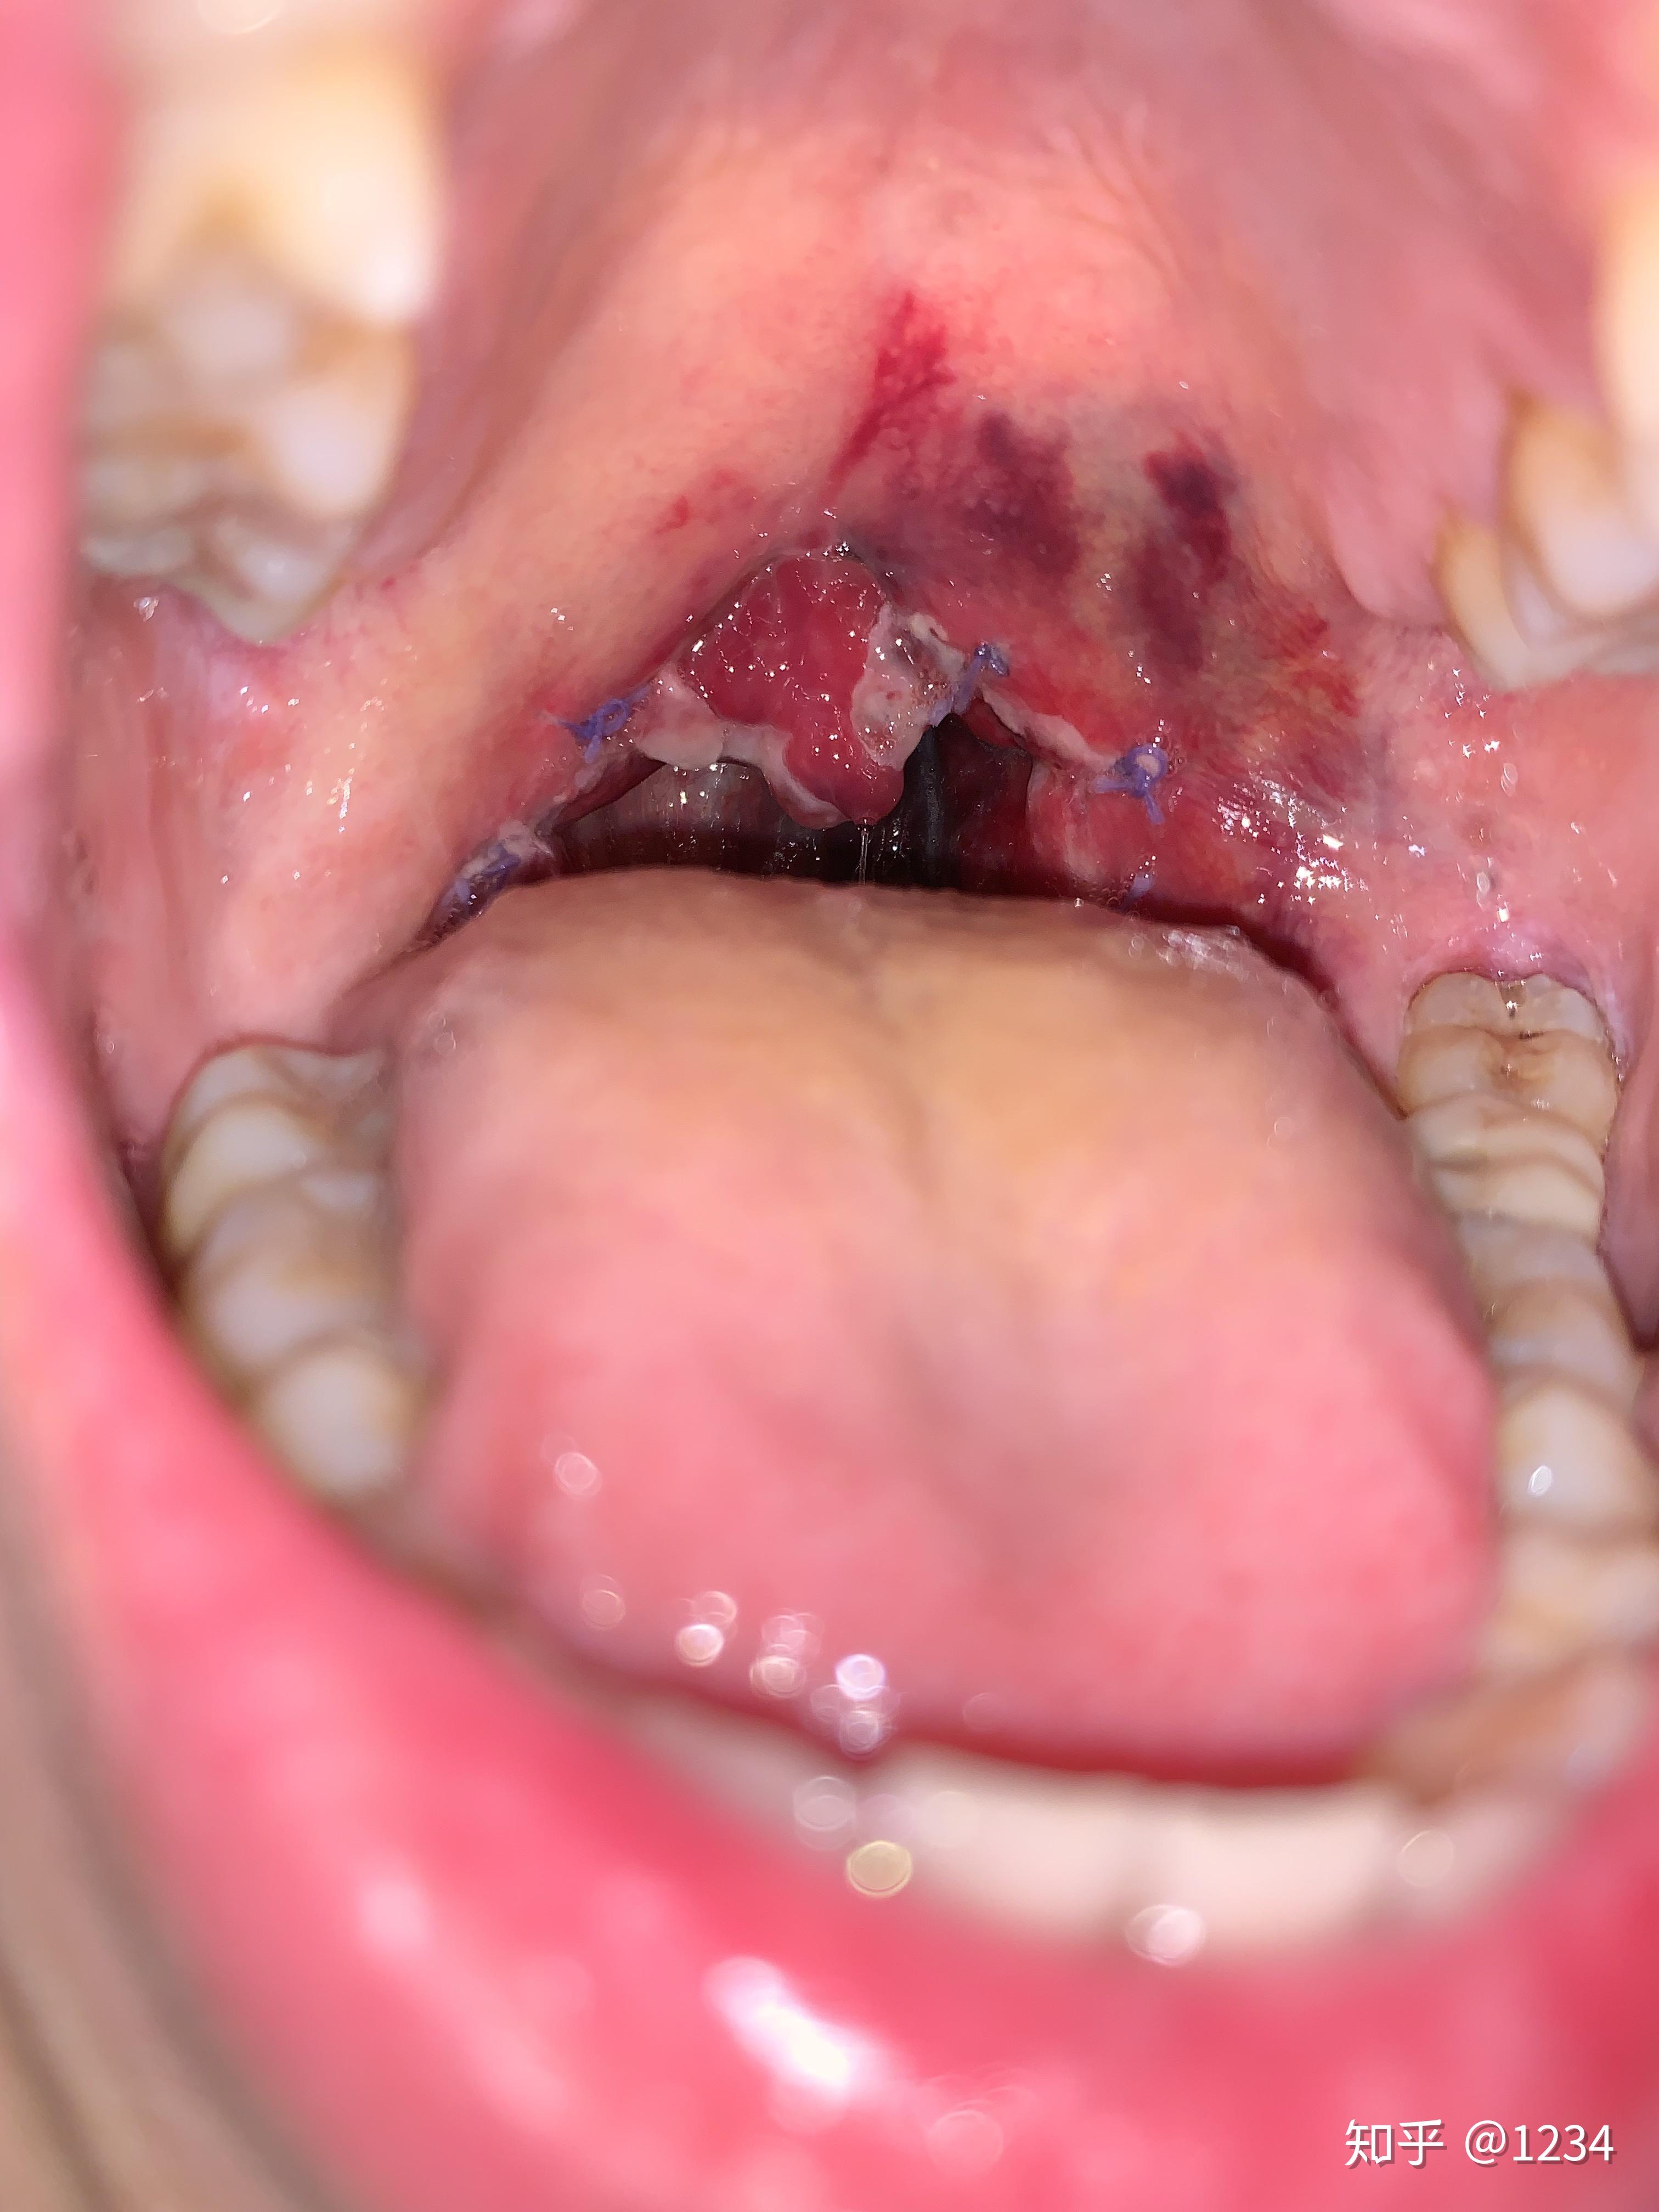

请问做扁桃体切除术需要一起做腭咽成形术吗? - 知乎

图片尺寸1536x2048